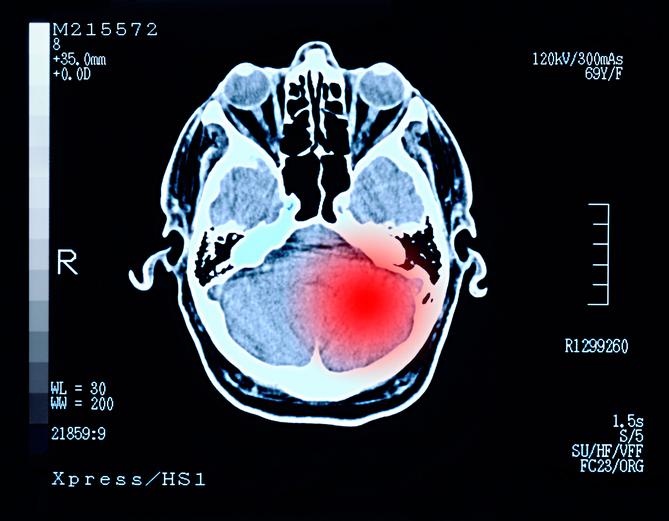

Un ensayo de la Universidad de Plymouth, busca comprobar que medicamentos para el VIH, tales como ritonavir y el lopinavir, pueden servir para tratar los tumores cerebrales.

Los antirretrovirales, medicamentos usados para tratar el VIH y el SIDA, podrían tener otro uso: el de reducir el crecimiento y la supervivencia de los tumores cerebrales en personas que padecen de neurofibromatosis 2 (NF2), trastorno causado por cambios en un gen llamado NF2.

Al menos eso es lo que intentan comprobar científicos del Centro de Excelencia en Investigación de Tumores Cerebrales de la Universidad de Plymouth, en el Reino Unido, quienes trabajan en un ensayo médico llamado ‘Retreat’, con ayuda del ritonavir y el lopinavir.